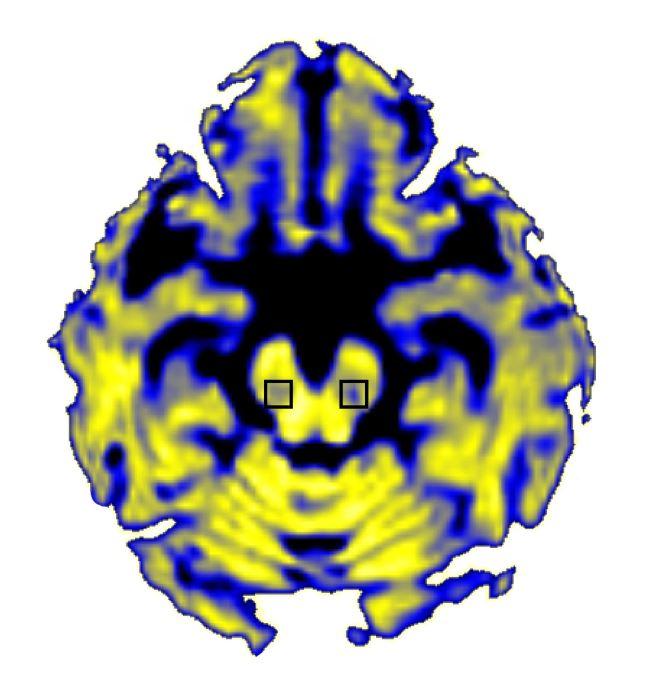

The researchers, led by David Vaillancourt, Ph.D., a professor of applied physiology and kinesiology at the University of Florida in Gainesville, FL, used a form of MRI that differentiates between water contained in brain cells and "free" water outside of cells. Their analysis focused on the substantia nigra, a brain structure where Parkinson's disease kills neurons that use the chemical dopamine to communicate with other cells. The results showed that the amount of free water in that brain area stayed the same over the course of a year in healthy individuals but increased in early-stage Parkinson's patients during that period and increased further over the next three years. This confirms and expands on a prior study by the same group that measured free water over just one year. The new findings also revealed the increase in free water was linked to worsening symptoms.

Parkinson's disease destroys dopamine-producing cells in the substantia nigra, which connect to adjacent brain areas. Dr. Vaillancourt's study showed that a greater free water increase in the substantia nigra was associated with a decrease in dopamine neuron activity in one of these nearby regions, supporting the idea that free water changes are related to progression of the disease.

How Parkinson's disease alters the brain: NIH-funded scientists have discovered that Parkinson's disease increases the amount of "free" water in a particular brain area. Image courtesy of David Vaillancourt, Ph.D., University of Florida.